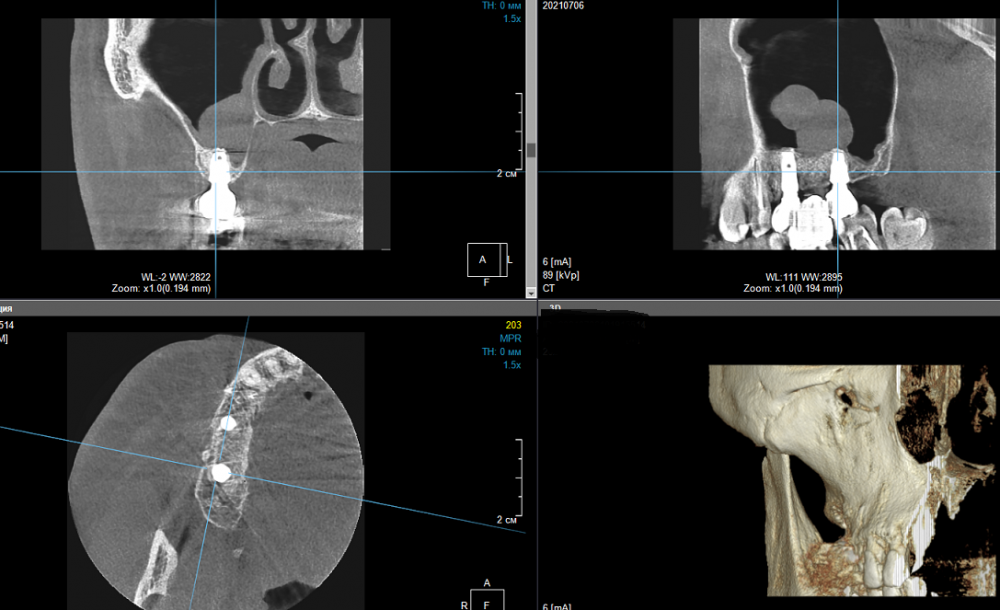

еатегsffhgj Опубликовано 6 июля, 2021 Автор Поделиться Опубликовано 6 июля, 2021 я сделал скрины. разные. Ссылка на комментарий

Irouil Опубликовано 16 июля, 2021 Поделиться Опубликовано 16 июля, 2021 Скорее всего речь идёт о костном остром крае, на одном из предоставленных срезов просматривается подобный контур гребня Если не беспокоит - не обязательно что-то делать, но можно превентивно сделать небольшой разрез и сошлифовать его Ссылка на комментарий